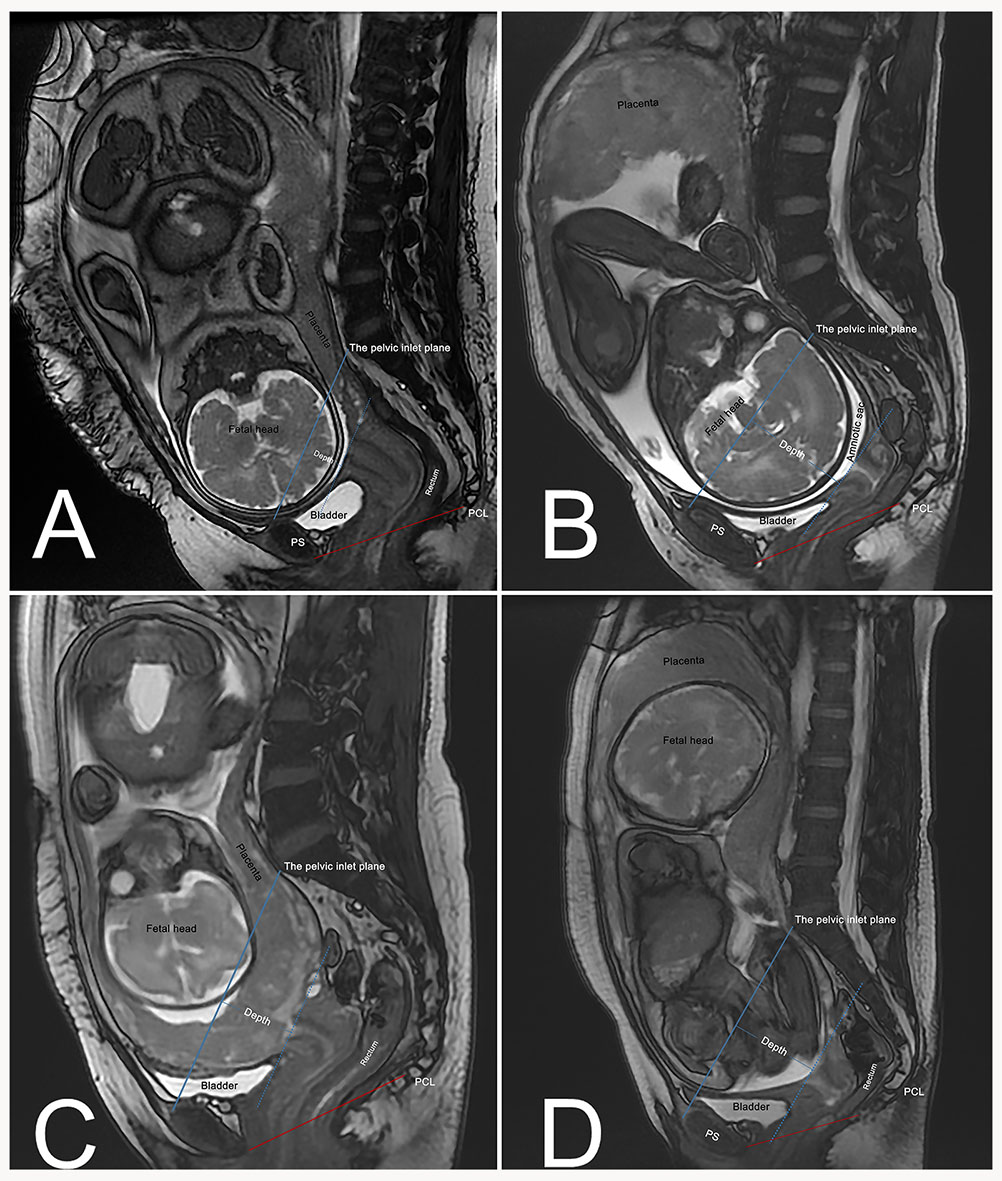

The pubococcygeal line (PCL), the recommended MRI reference line for diagnosing POP, extends from the pubic symphysis’s inferior aspect to the last coccygeal joint [19]. Perpendicular distances from the PCL to the bladder neck (BN), the cervix’s most distal edge (C), and the posterior fornix’s apex (PF) were measured (Fig. 1). Organ-specific reference points above the PCL had positive values (+), while those below had negative values (–).

Fig. 1. Sagittal MRI-based measurement of pelvic organ positions relative to the pubococcygeal line (PCL). PCL is the red line from pubic symphysis to the last coccygeal joint. Perpendicular distances from the PCL to anatomical points BN, C, and PF are measured (denoted by short red lines) in non-pregnant women (A) and pregnant women with cephalic presentation (B). BN, bladder neck; C, most distal cervical edge; MRI, magnetic resonance imaging; PF, apex of the posterior fornix; PS, pubic symphysis.